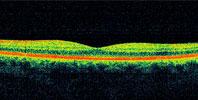

Optical Coherence Tomography (OCT) is a new imaging technique which produces a cross sectional image of the retina. The retina actually is composed of ten different layers of tissue, each layer having a specific function. Each retina is scanned with infra red light which is reflected back into the instrument. Each layer of retinal tissue has a specific reflectance value which is interpreted by the instrument and this reflectance is then translated into an image. The doctor then may view this cross section of retina to determine if any problem exists. The instrument takes a mere three seconds to scan each retina.

Normal OCT scan

Here we can view the cross section of the retina. The different colored horizontal bands represent different layers of retinal tissue. The dip in the middle of the image is normal as the center of the dip represents the special area of the retina known as the macula. This is an image of a normal retina.